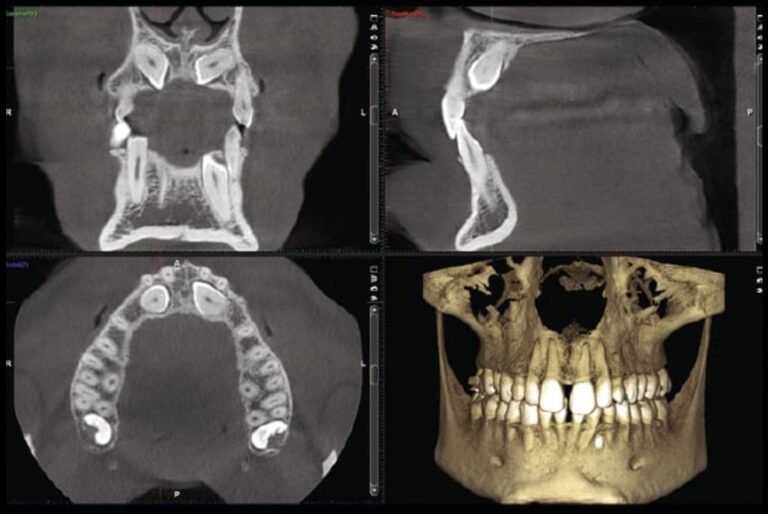

Denti del giudizio: quando serve la CBCT a Torino

Implantologia

La CBCT prima di togliere un dente del giudizio non è un esame di routine: serve quando la radice del dente si…